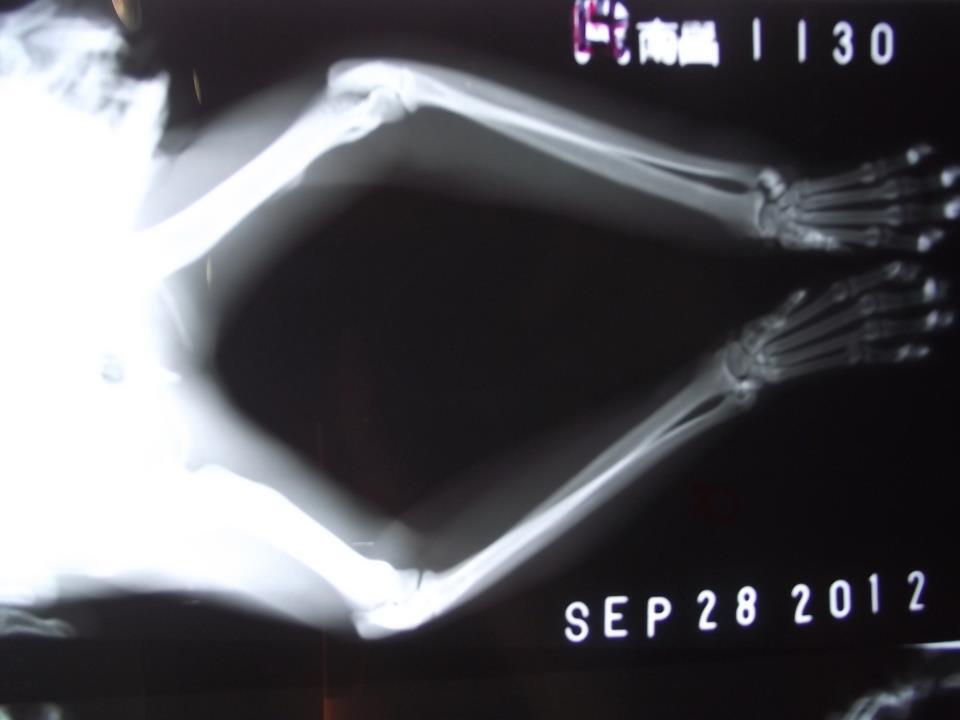

最後黑貓出現了,也順利誘捕,送到醫院檢查後,他的一眼已經萎縮,不

需要處理了,而掰咖的原因,照X光,是曾斷過,但癒合了,變成長短腳

所以走路看起來掰咖的樣子,但口腔狀況確不好,有很多牙齒都爛了,也

有牙結石,給予拔除蛀牙及洗牙,並結紮植入晶片後放回原地。